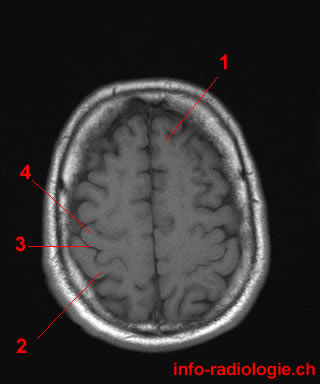

1. What is it?

19. What is the medical term for a groove that separates the two hemispheres of the brain?

The interhemispheric fissure is also known as the longitudinal cerebral fissure, which is the deep groove that separates the two hemispheres of the brain. The other options do not specifically refer to this brain structure.